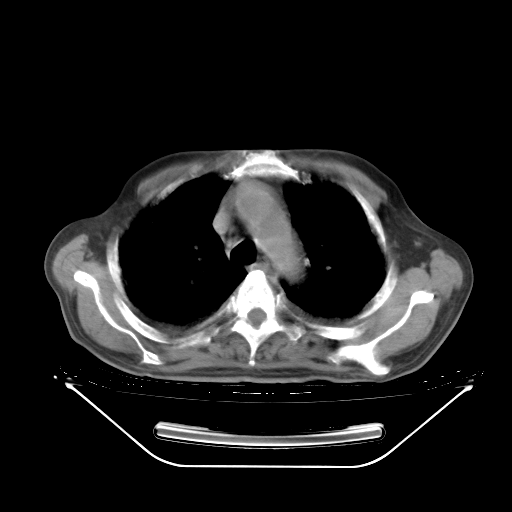

今天复查肺部CT,发现双肺广泛磨玻璃样改变。所以我把3月19日和5月9日相隔50天的肺部CT上传。请大家会诊。

5月9日肺部CT(在4月27日齐鲁医院肺部CT描述部分肺组织磨玻璃样改变,12天后肺组织广泛磨玻璃样改变)

大致读了系列胸部CT:纵隔窗无明显异常,肺窗:从4、27至今:主要是双肺中下野外带可见毛玻璃样改变,目前处于急性肺泡炎阶段,至于原因考虑1、结替组织或胶原血管性疾病所致?2、恶性疾病如恶组在肺部所致的表现或细支气管肺泡癌?3、药物或其它原因如肺蛋白沉着症所致肺泡炎目前不太可能?总之,明天就去请我院的呼吸科、感染科、血液科和临免专家会诊哈。